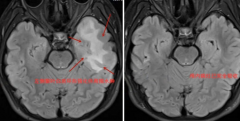

• 14岁少年睡梦中突发癫痫,竟因与一动物亲密接触

• 14岁少年睡梦中突发癫痫,竟因与一动物亲密接触……

弓形虫 俊俊 排泄物 2024/11/22